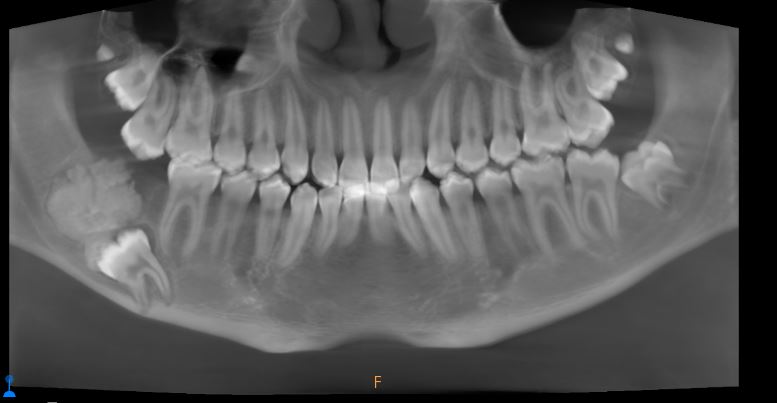

The family sought advice from several healthcare professionals who identified the rare nature of the swelling in the mouth. Since this required special treatment, Salem was eventually referred to Dr. Farzin Sarkarat, a specialist oral and maxillofacial surgeon at Medcare Dentofaces in Dubai. Concerned by the severity of the swelling in the boy’s jaw and the displacement of Salem’s right third molar tooth, Dr. Farzin conducted a thorough analysis.

“The position of the swelling was dangerously close to the inferior alveolar nerve, a critical nerve responsible for sensations in the lower teeth, chin, and lower lip. The tumor’s proximity to the nerve made the situation extremely delicate, since any oversight could result in permanent nerve damage. This made the case highly complex. From the initial evaluation, it was clear that Salem’s condition was more than a simple swelling,” explained Dr. Farzin.

“Detailed imaging and diagnostic tests revealed that Salem suffered from Ameloblastic Fibroma, a rare benign tumour originating from dental tissue that typically affects younger individuals. While non-cancerous, the tumour caused significant swelling, pain, and displacement of Salem’s teeth,” he added.

“If left untreated, the tumour could have grown larger, damaging the surrounding bones and nerves, leading to facial deformities or even loss of sensation in the jaw,” said Dr. Farzin. “We decided to perform a surgical procedure to remove the tumor, preserve the nerve, and restore Salem’s jaw.”

Dr. Farzin’s team designed a meticulous treatment plan that involved removing the tumor and impacted wisdom tooth, repositioning the nerve, and using a bone plate to reconstruct the jaw. Every step required extreme precision to avoid nerve damage and ensure Salem could regain full jaw functionality.